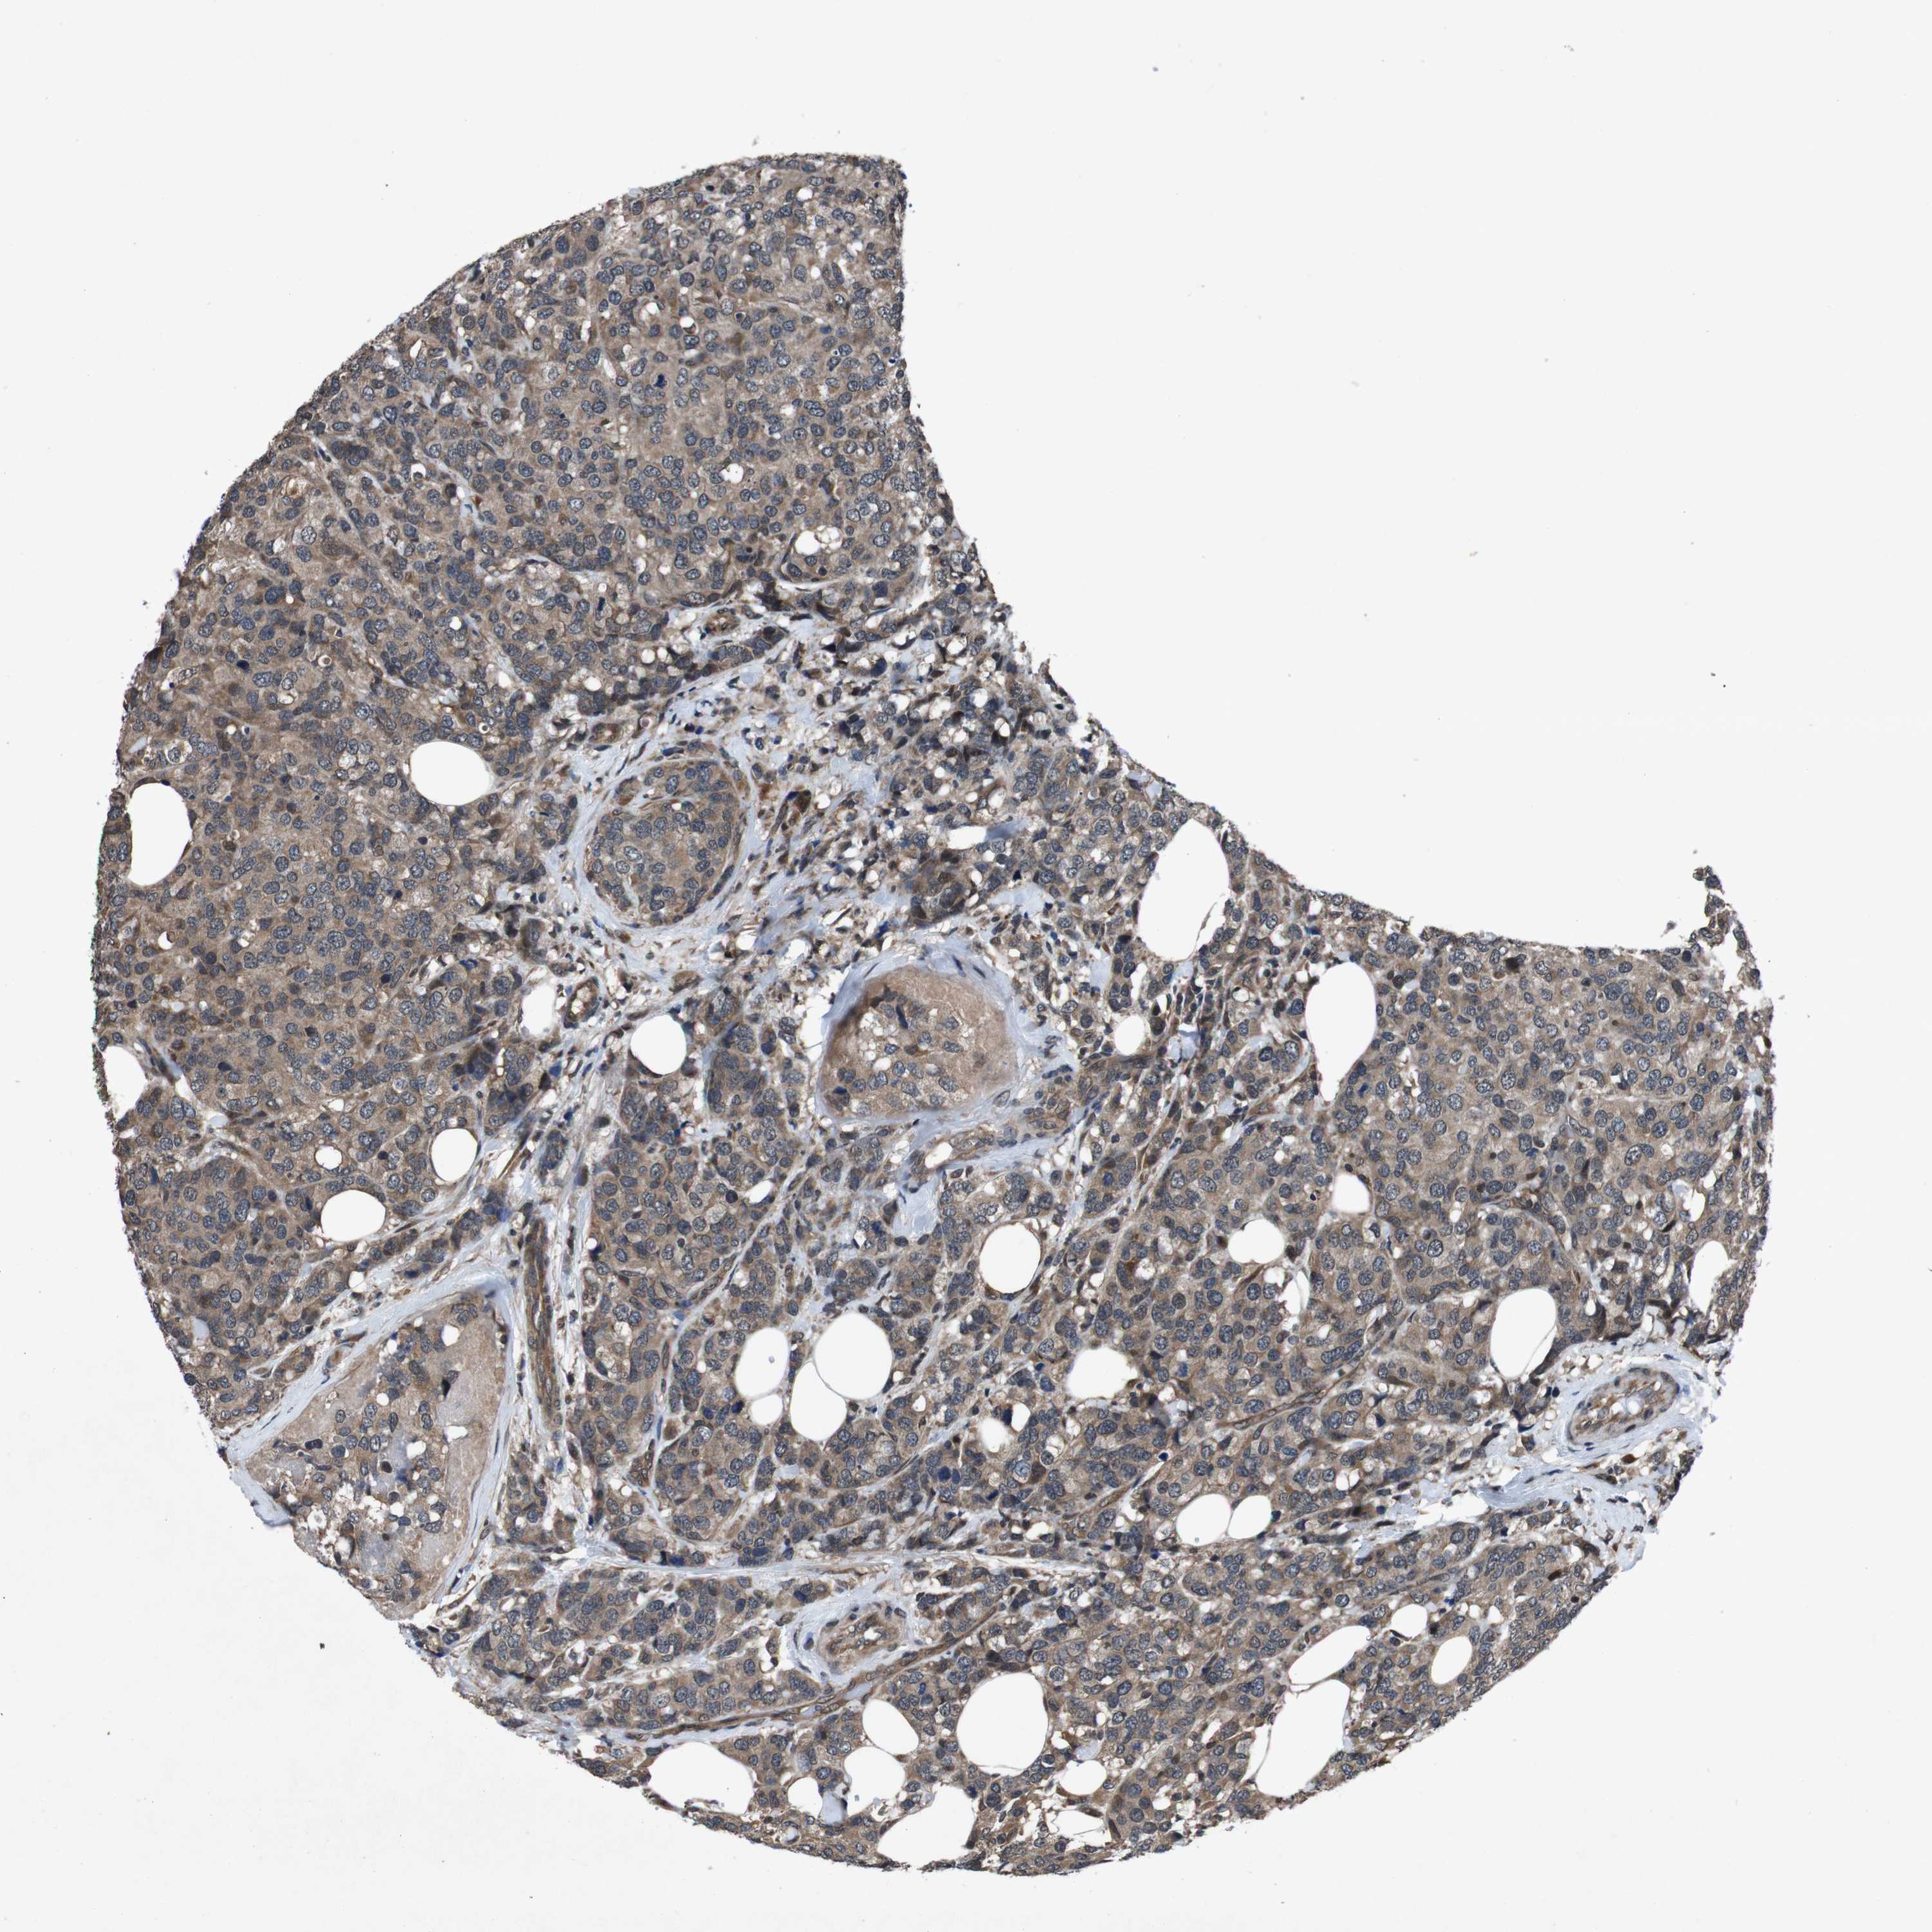

BRCA TCGA BRCA VALIDATION PROTEIN EXPRESSION

ANTIBODIES

AND

VALIDATION